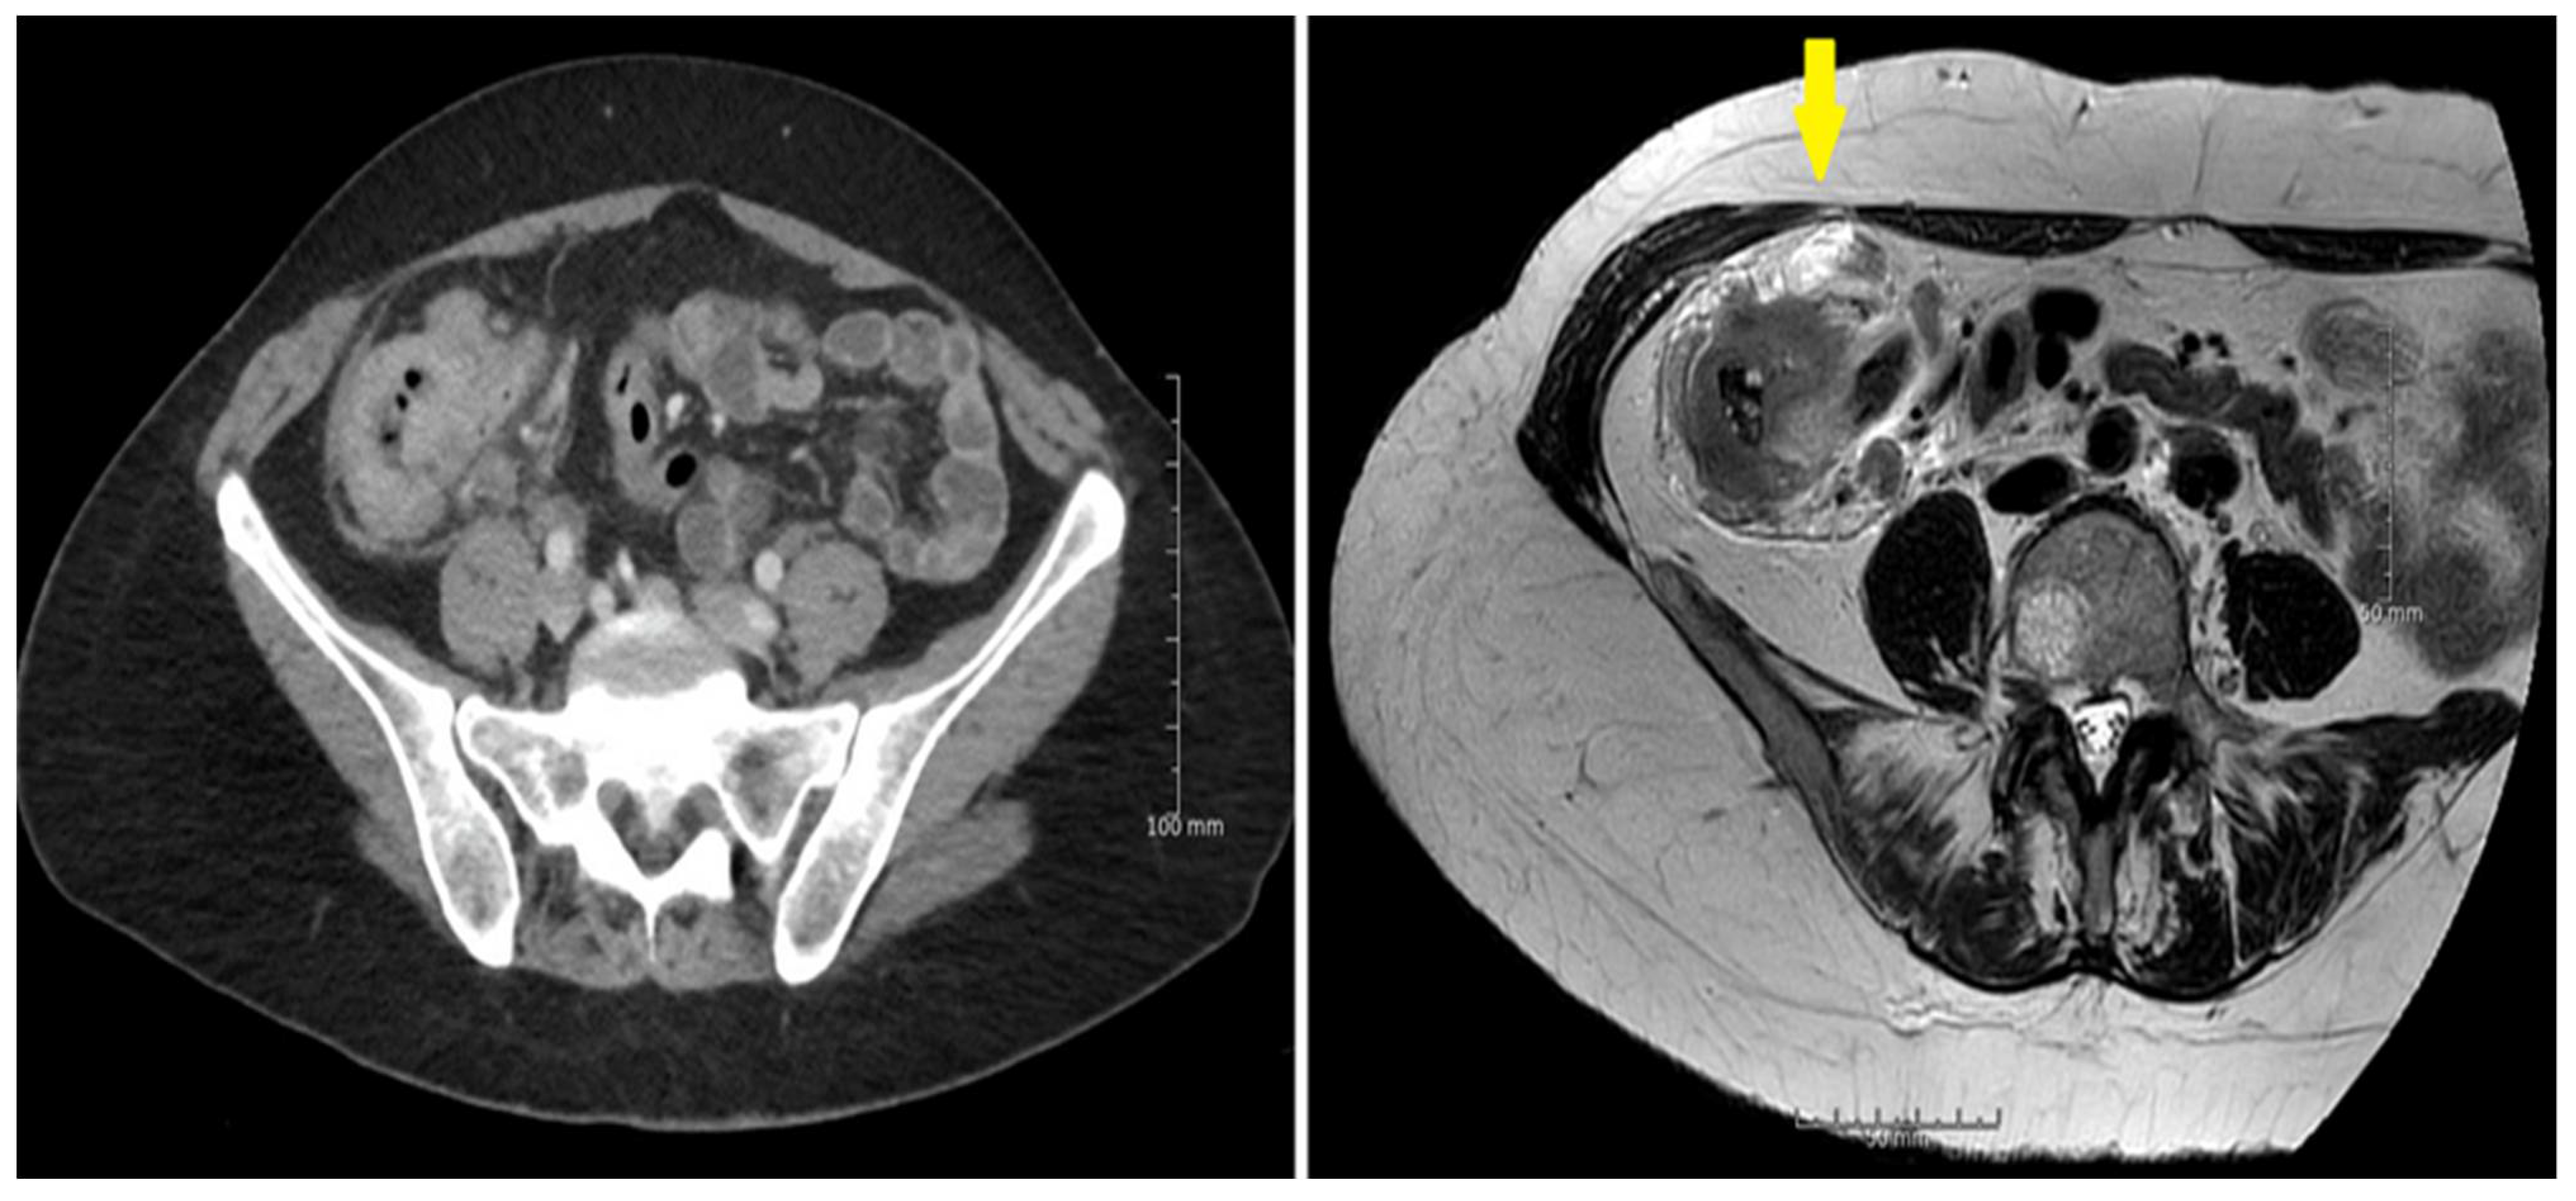

3. Results

3.2. Sensitivity and Specificity

3.3. Diffusion Weighted MRI